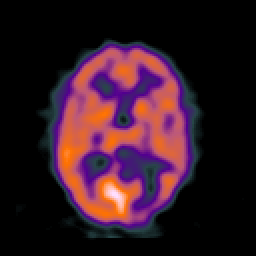

SPECT TC Study #6 -- Slice #30

[Home][Help][Clinical][Tour 1][Tour 2][Tour 3] Slice 30